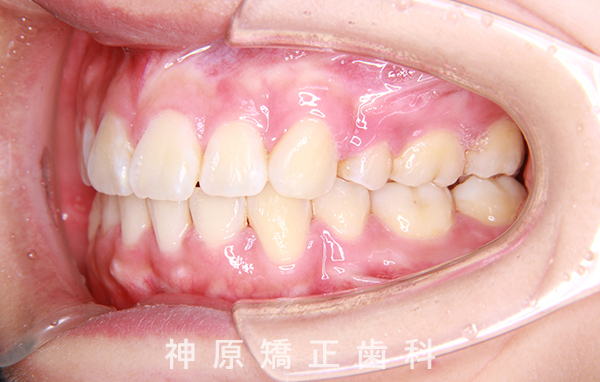

治療終了

口元の突出感と下の歯並びの乱れを改善するため、小臼歯を抜歯することにしました。抜いたスペースを利用して、前歯をできるだけ後ろに移動させるため、上下に歯科矯正用アンカースクリューを使用する計画を立てました。治療の目標について同意を得た後、矯正治療を開始しました。歯の動きが順調で、1年9カ月で治療が完了しました。その結果、側貌はE-lineに調和したバランスの良い仕上がりになりました。